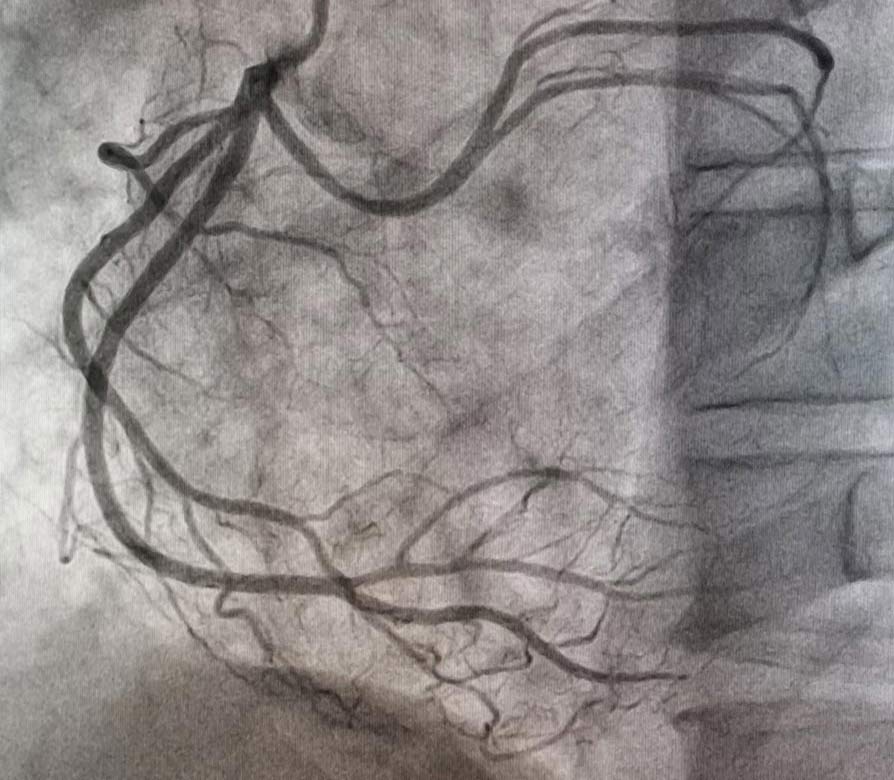

The coronary angiogram revealed left system without lesions, ectatic RCA with acute total occlusion in the middle segment with grade 5 thrombus, and anomalous origin of the circumflex coronary artery arising from the proximal segment of the RCA with fusiform aneurysm in its middle portion (Figure 4 and Figure 5).

Figure 4.

Figure 5.